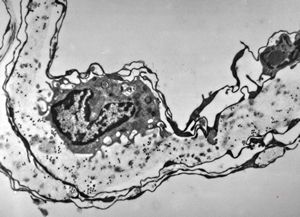

F,31y. | demyelinating hypertrophic neuropathy - n. suralis- bands of Büngner with collagen-filled pockets